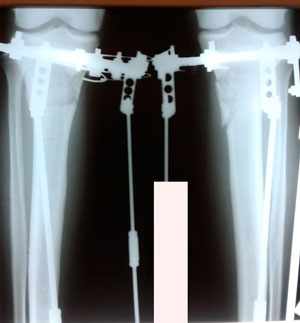

на фиксации

IMG_7142-18-11-19-07-45.JPG

IMG_7144-18-11-19-07-45.JPG